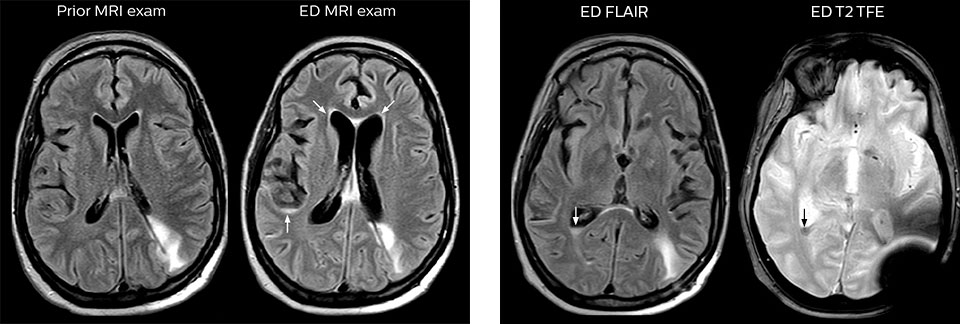

The high value of a negative MRI scan

“One of the most important decisions an ED physician has to make is to admit or discharge their patient. So a physician who is better informed by an MRI exam can make this decision with more confidence. By converting to a test that has a far better potential to identify issues, physicians get a better and more certain diagnosis."

"In my experience a negative MRI, because it is so sensitive to abnormality, far exceeds the value of a negative CT. A negative MRI can allow physicians to be more confident about making discharge decisions, potentially reducing the number of admissions in cases of doubt, and offering cost savings for the institute."

“There are far more decisions being made to send people home than to admit. And in terms of making that decision, I believe there’s no more valuable exam than a negative MRI for neurologic disorders.”